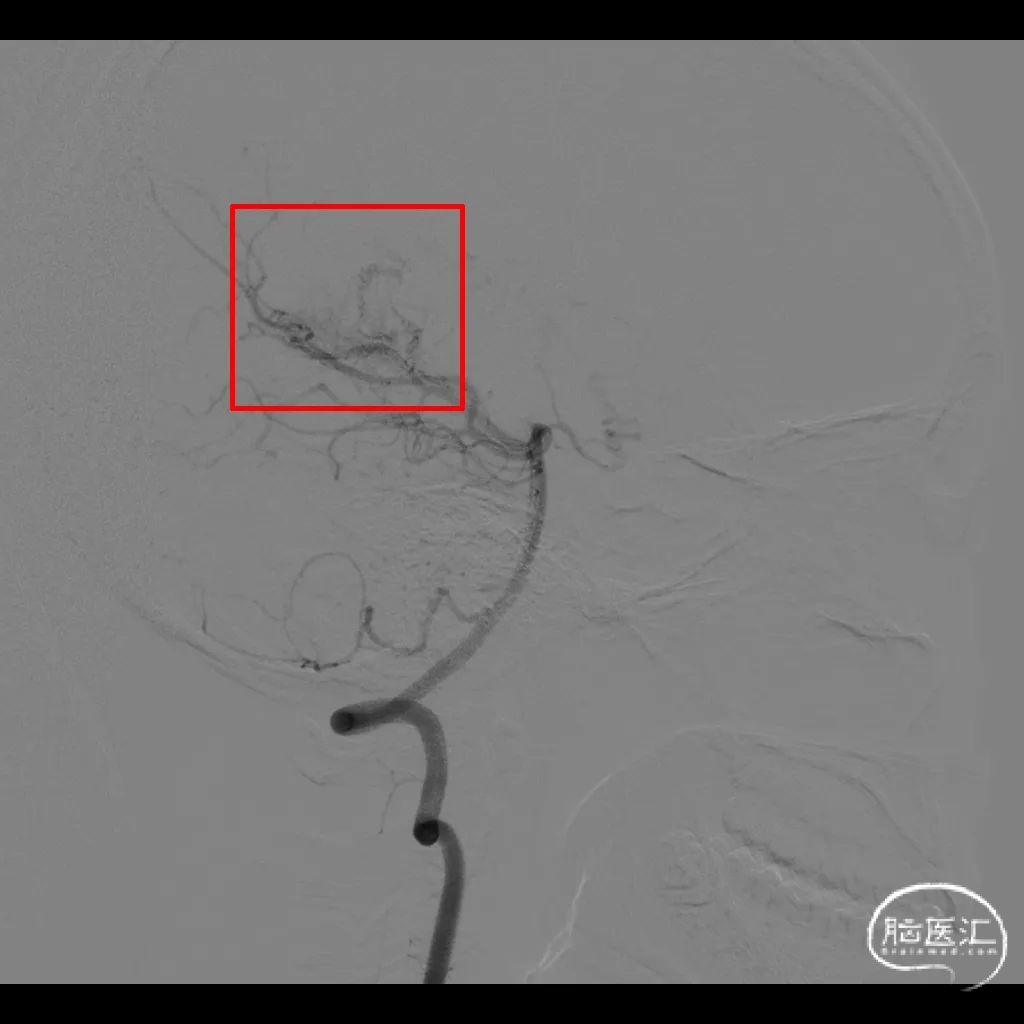

图2. DSA提示右侧脑室后角畸形血管团,由脉络膜后动脉供血。